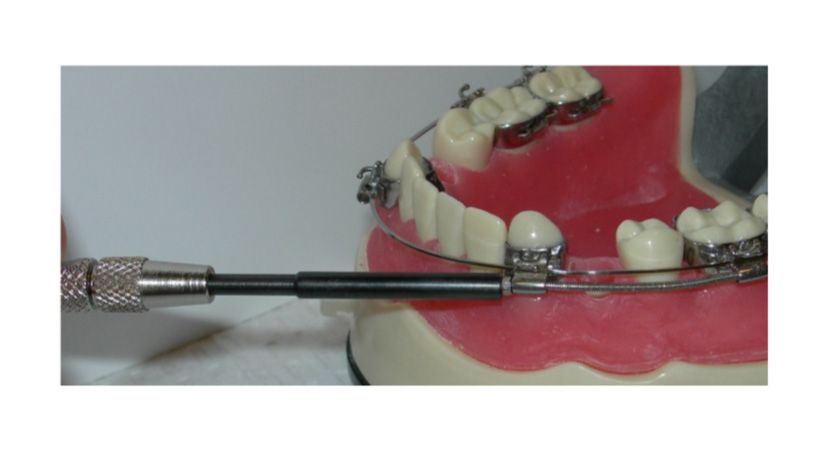

Movimiento acelerado de los dientes de ortodoncia

Técnicas quirúrgicas y el fenómeno acelerador regional